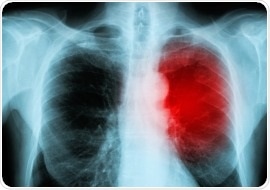

Cancer immunotherapy can lead to inflammation of the heart muscle

Image Credit: AdobeStock